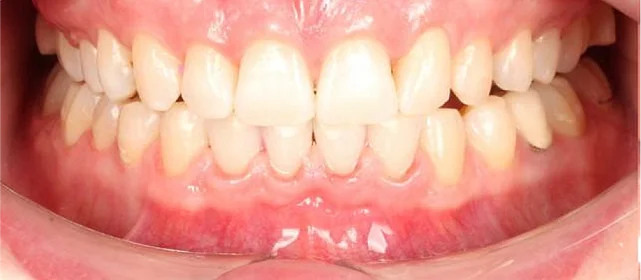

Результат

полное выравнивание зубных рядов без удаления зубов. Рецессия десны не прогрессировала (контроль по КТ через 12 месяцев). Пациентка носит несъёмные ретейнеры

и ночные капы.